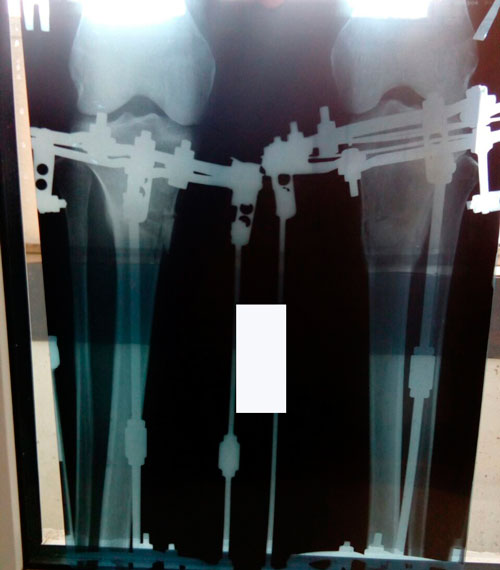

Рентген и ножки в 60 дней.